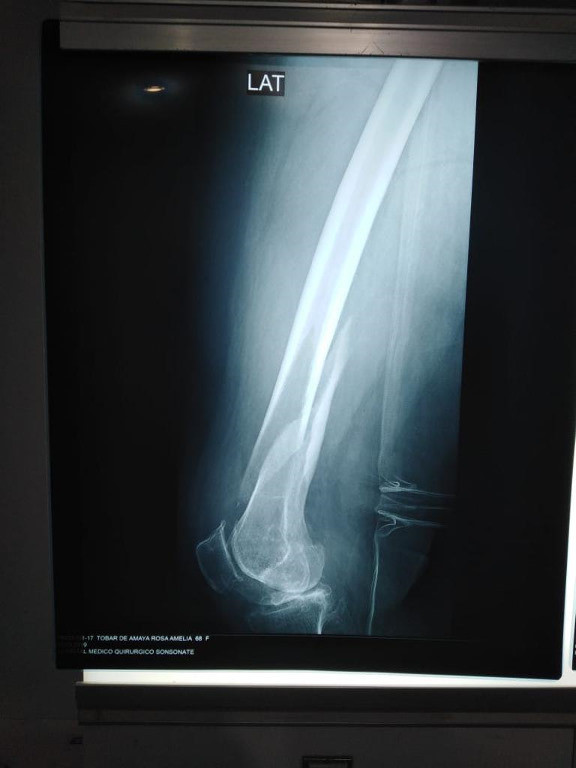

Imágenes de ortopedia y traumatología

Envíado por Dr. José Israel Flores Hernández